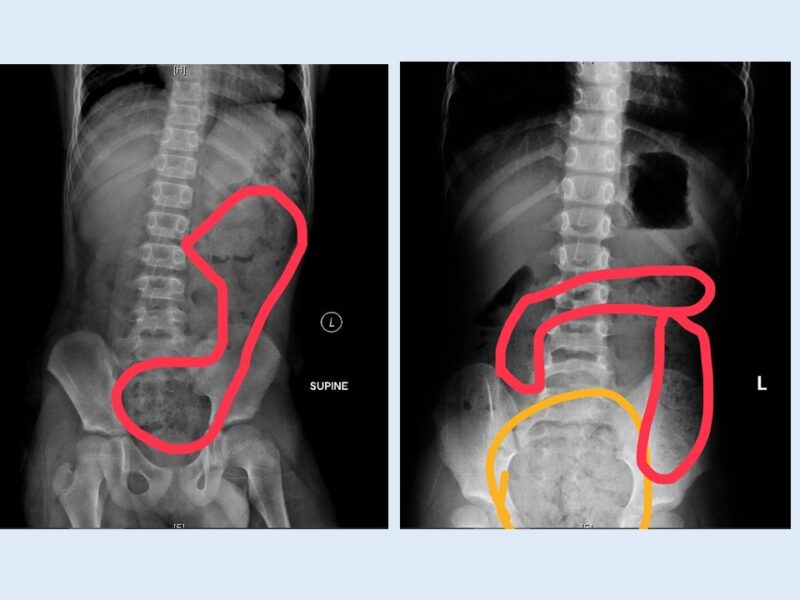

高雄某醫院兒科急診主治醫師蕭宇超分享數個臨床案例,一名11歲的小學五年級男生,因突發腹痛、冒冷汗、嘴唇發紫、手腳冰冷而被緊急送醫。經過問診、觸診及腹部X光檢查,確診為嚴重便秘。灌腸後,男童排解大量糞便,症狀立即緩解。男童母親提到,孩子習慣邊上廁所邊玩手機,常因被催促才匆忙起身,根本不確定自己是否排乾淨。

另一名6歲的小一女童,則是因為肚子痛得大哭,腹部異常脹大。X光顯示她「一肚子大便」。媽媽猜測,孩子剛上小學,可能還沒習慣學校的作息與如廁環境,有便意也忍著不去,連好幾天沒排便都沒察覺,直到嚴重才送急診。此外,還有周歲女嬰因大便乾硬如「羊糞」、帶有鮮血及肛裂求診。女嬰媽媽表示,換副食品後便開始便秘。醫師除了衛教調整副食品內容,也開立軟便藥,以減輕排便疼痛,修復肛裂。